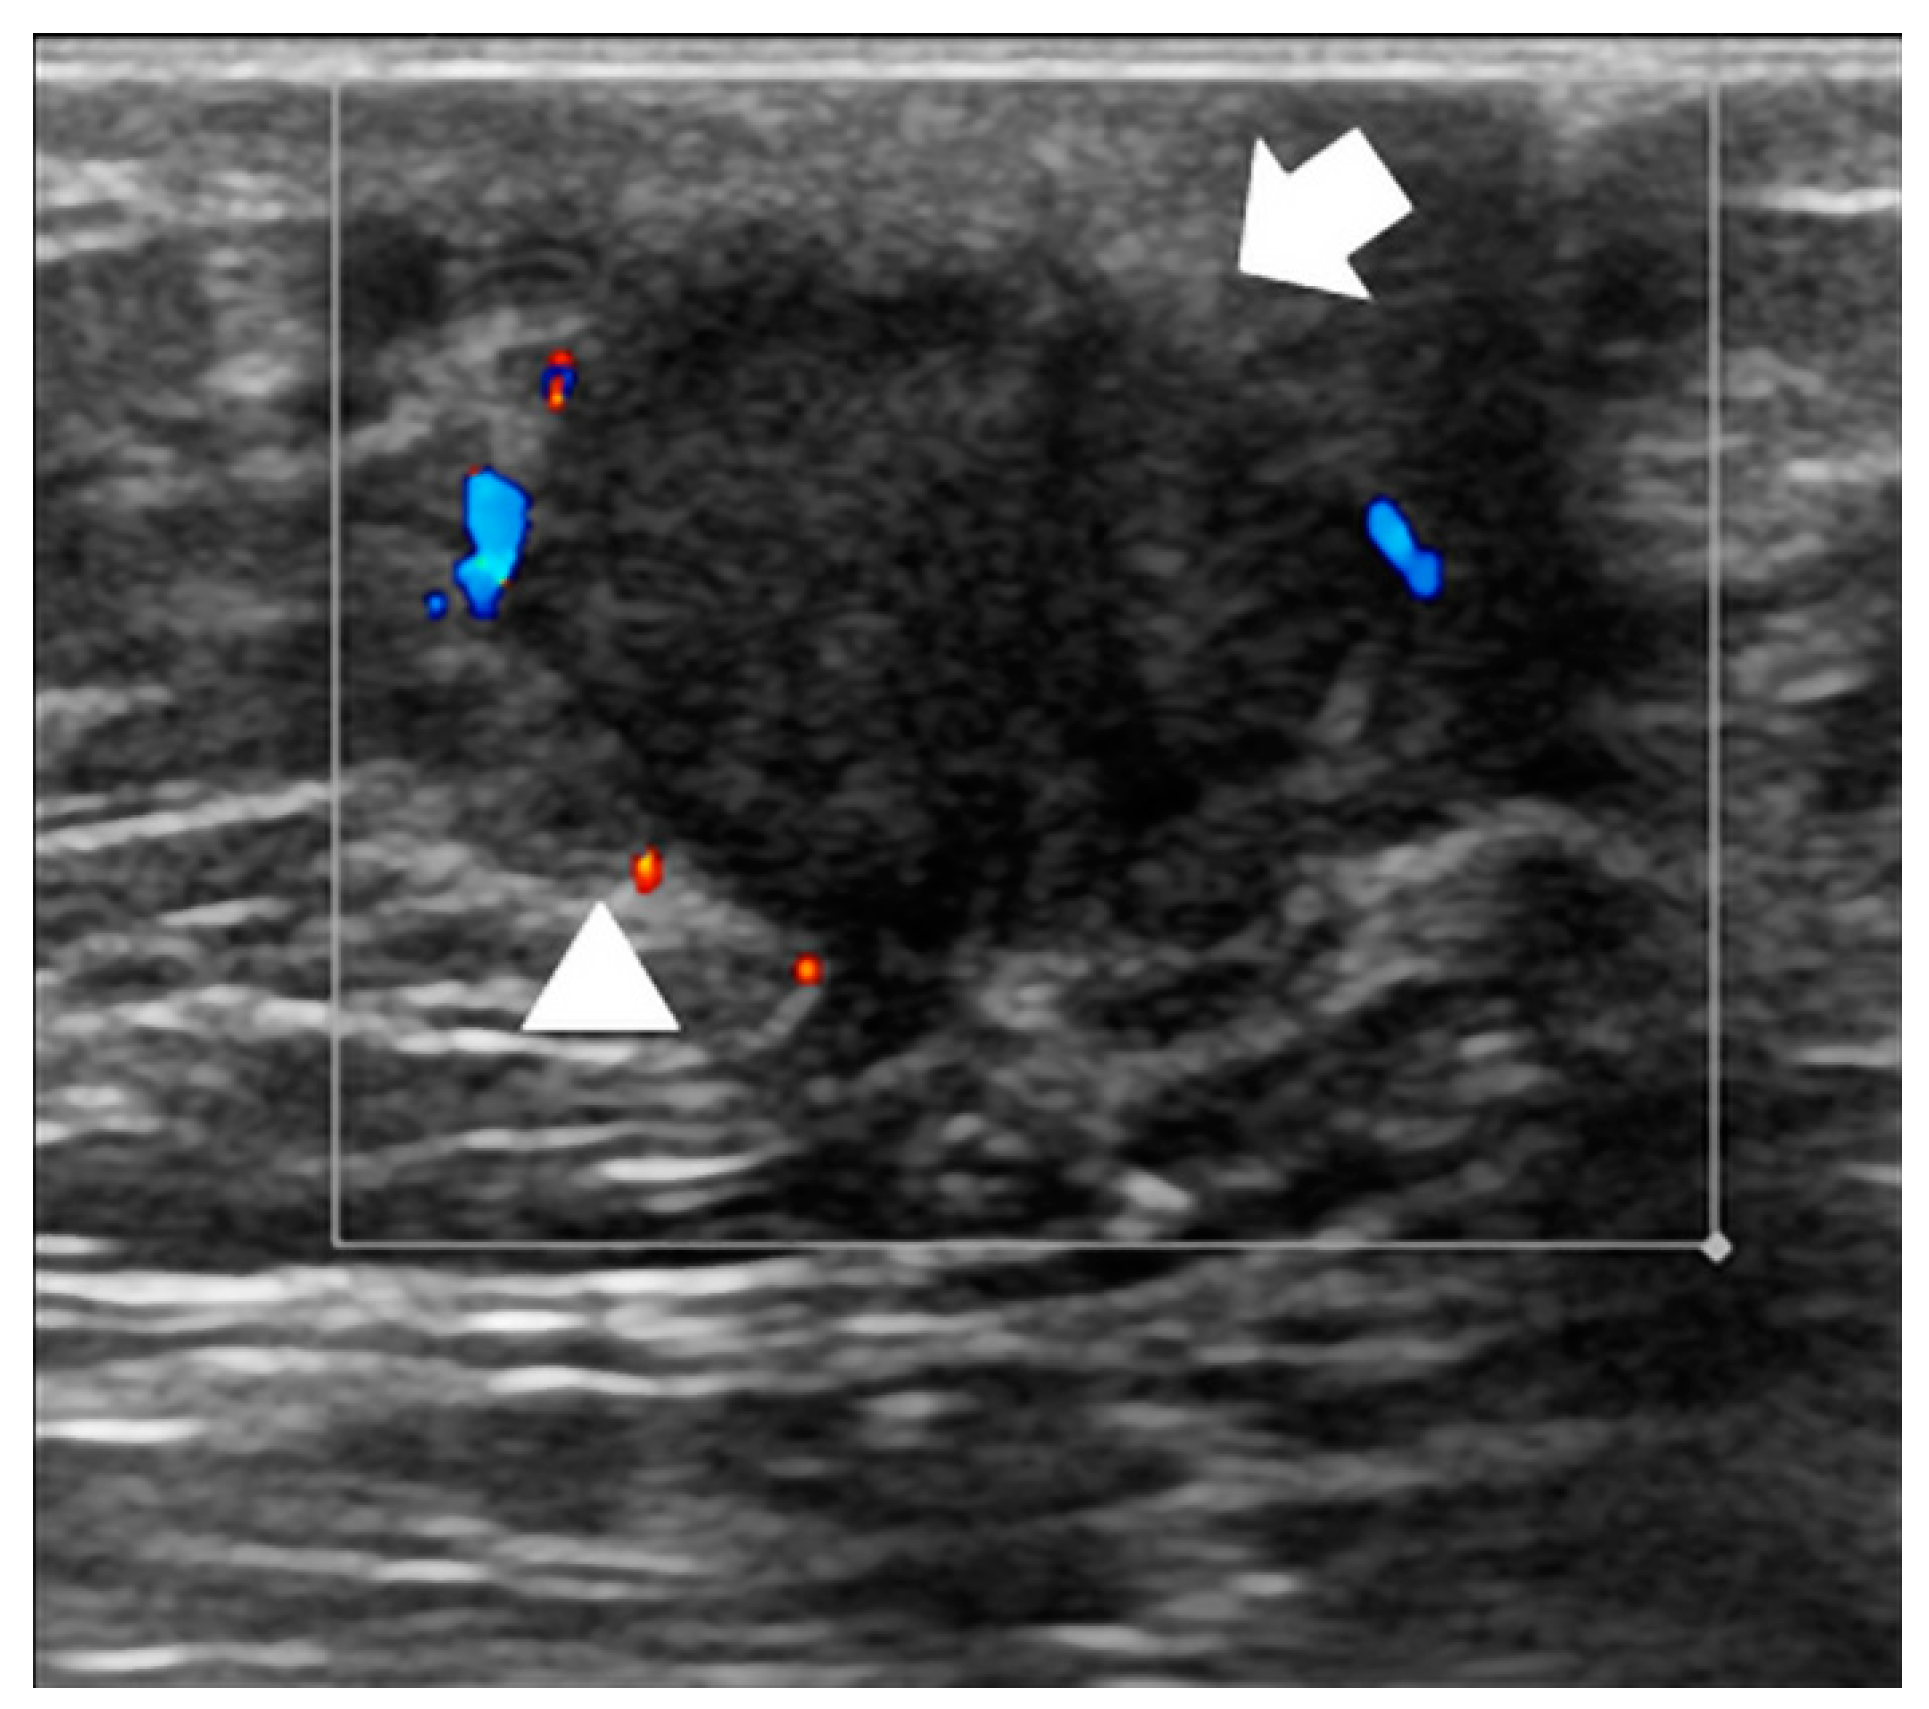

3.3. US Features

| Type of ultrasound lesion, N (%) | Solid mass | 41 (89) |

| Mixed mass | 5 (11) | |

| Margins of the mass, N (%) | Poorly defined | 18 (39) |

| Smooth | 15 (33) | |

| Spiculated | 13 (28) | |

| Mass taller than wide, N (%) | No | 29 (63) |

| Yes | 17 (37) | |

| Echogenity, N (%) | Inhomogeneous | 44 (96) |

| Homogeneous | 2 (4) | |

| Color Doppler, N (%) | Absent | 3 (7) |

| Internal | 14 (33) | |

| Predominantly in the rim | 26 (60) | |

| Missing | 3 | |

| Posterior acoustic enhancement, N (%) | No | 41 (89) |

| Yes | 5 (11) |